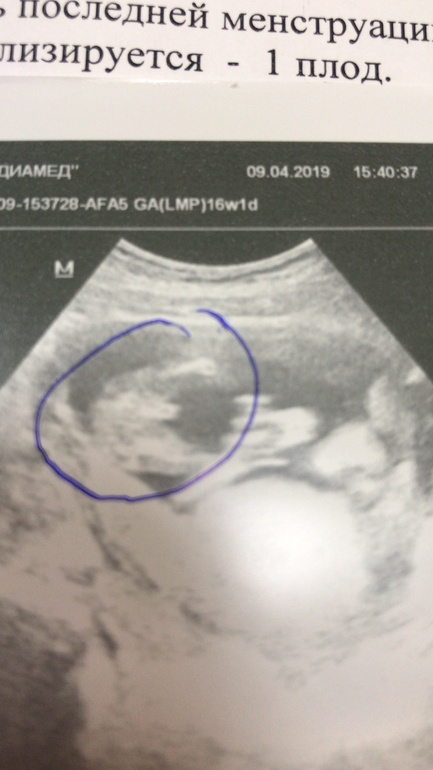

А нам вот такую девочку обещают😁😁. УЗИ где-то на 19 неделе

в 16 неделек)